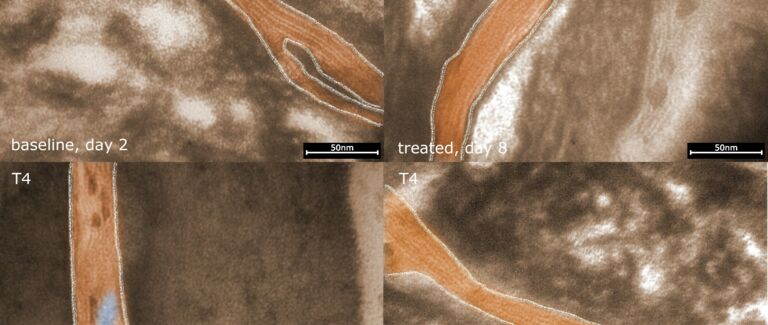

Microscopy Services setzt das patentierte Analyseverfahren Lipbarvis® (Lipid Barrier Visualisation, LBV) ein, um die epidermale Hautbarriere direkt ohne invasive Probenahmen untersuchen zu können.

Ihre wissenschaftliche Arbeit in Diagnostik und Wirkstoff-Entwicklung wird durch unsere elektronenmikroskopischen Untersuchungen und Bilddokumentationen im wahrsten Sinne des Wortes anschaulich erklärt und deutlich beschleunigt.